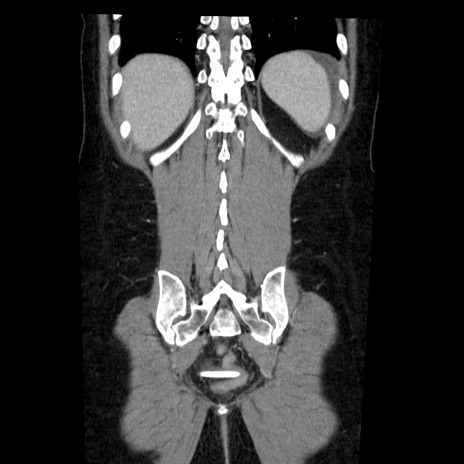

症例6(冠状断像)

【症例】50歳代女性

【主訴】下腹部痛

【既往歴】卵巣癌術後(8年前に当院で卵巣摘出)

【身体所見】 意識清明、腹部:平坦、腸蠕動音→、やや硬、下腹部自発痛・圧痛あり、反跳痛あり、筋性防御なし。